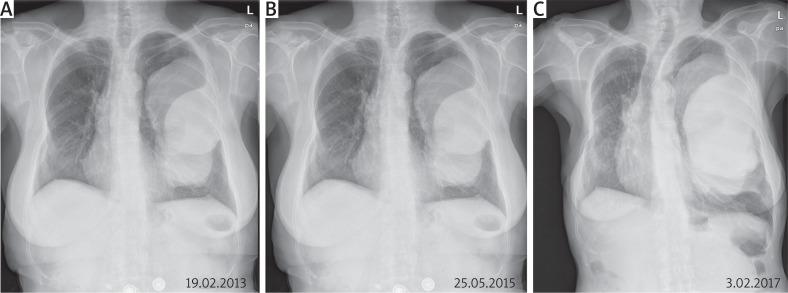

Solitary fibrous tumour along with non-small-cell lung cancer and Doege-Potter syndrome.

https://cdn.ncbi.nlm.nih.gov/pmc/blobs/cff5/6491374/ddb18e50aa8c/KITP-16-83948-g001.jpg